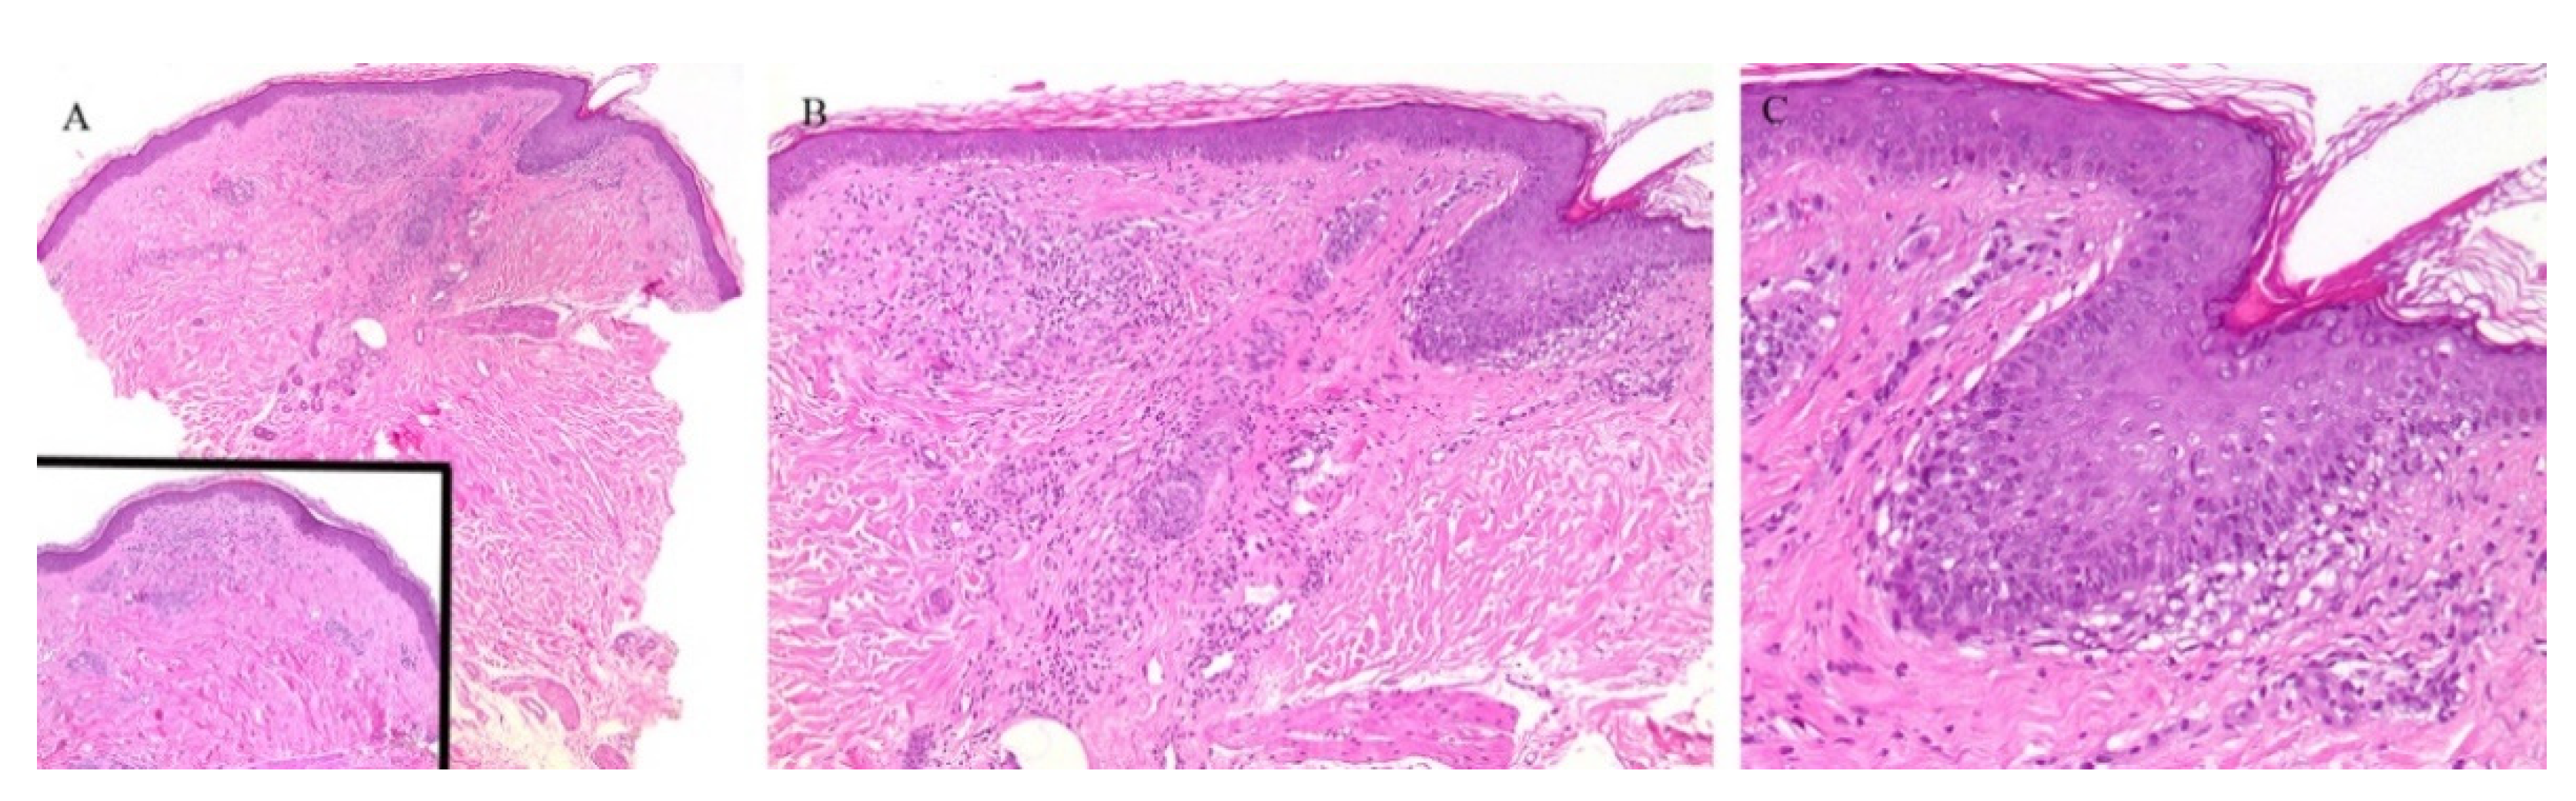

Clinically, the involvement of the hair follicle in GVHD can result in a variety of manifestations including non-scarring and scarring alopecias, a follicular rash, and comedonal lesions, among others [11]. Histologically, follicular variants have been described in both acute and chronic forms of GVHD (Figure 2) [12]. Unfortunately, the reported cases of acute follicular GVHD carried a high mortality rate while chronic follicular GVHD seems to confer a more favorable prognosis [13,14]. This involvement of the follicular epithelium has been attributed to inflammation around the bulge region of the hair follicle, likely due to the presence of stem cells in this area [15].

Figure 2.

(A–C) Graft versus host disease with perieccrine inflammation.

Eccrine gland involvement is also seen in GVHD. In addition to the classical histologic features, a lymphoplasmacytic infiltrate around the eccrine coils is a specific feature of GVHD (Figure 2) [16]. Eccrine squamous syringometaplasia has also been described in biopsy specimens of a patient with cutaneous and hepatic GVHD [17].